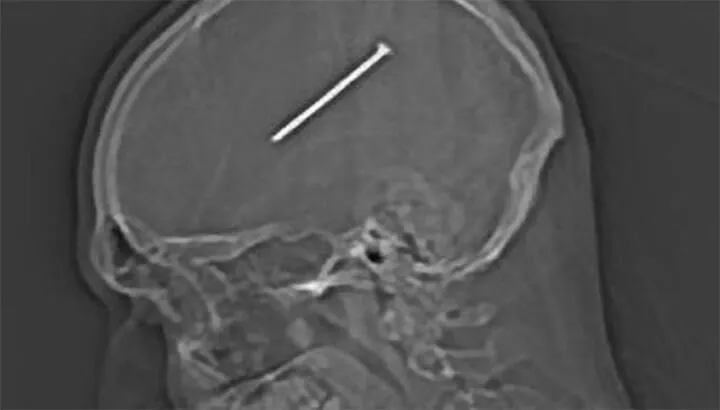

4. Man survives nail in brain

“Un-freaking-believable.” Those were the first words Dante Autullo spoke after doctors told him that they had removed an almost 4-inch nail from his brain. The Chicago man was stretching on a ladder when he slipped, which triggered the nail gun that blasted his head. At first, Autullo didn’t realize the projectile had pierced his skull.

In fact, Autullo waited 36 hours before seeking medical treatment. During that time he drove his snow plow, took his daughter to a rehearsal and had a nap. Finally, severe nausea and body aches prompted him to visit the hospital where physicians discovered the bizarre object in his cranium. Amazingly, Autullo suffered no major ill-effects, but I guess you could say he redefined the meaning of “hitting the nail on the head.”